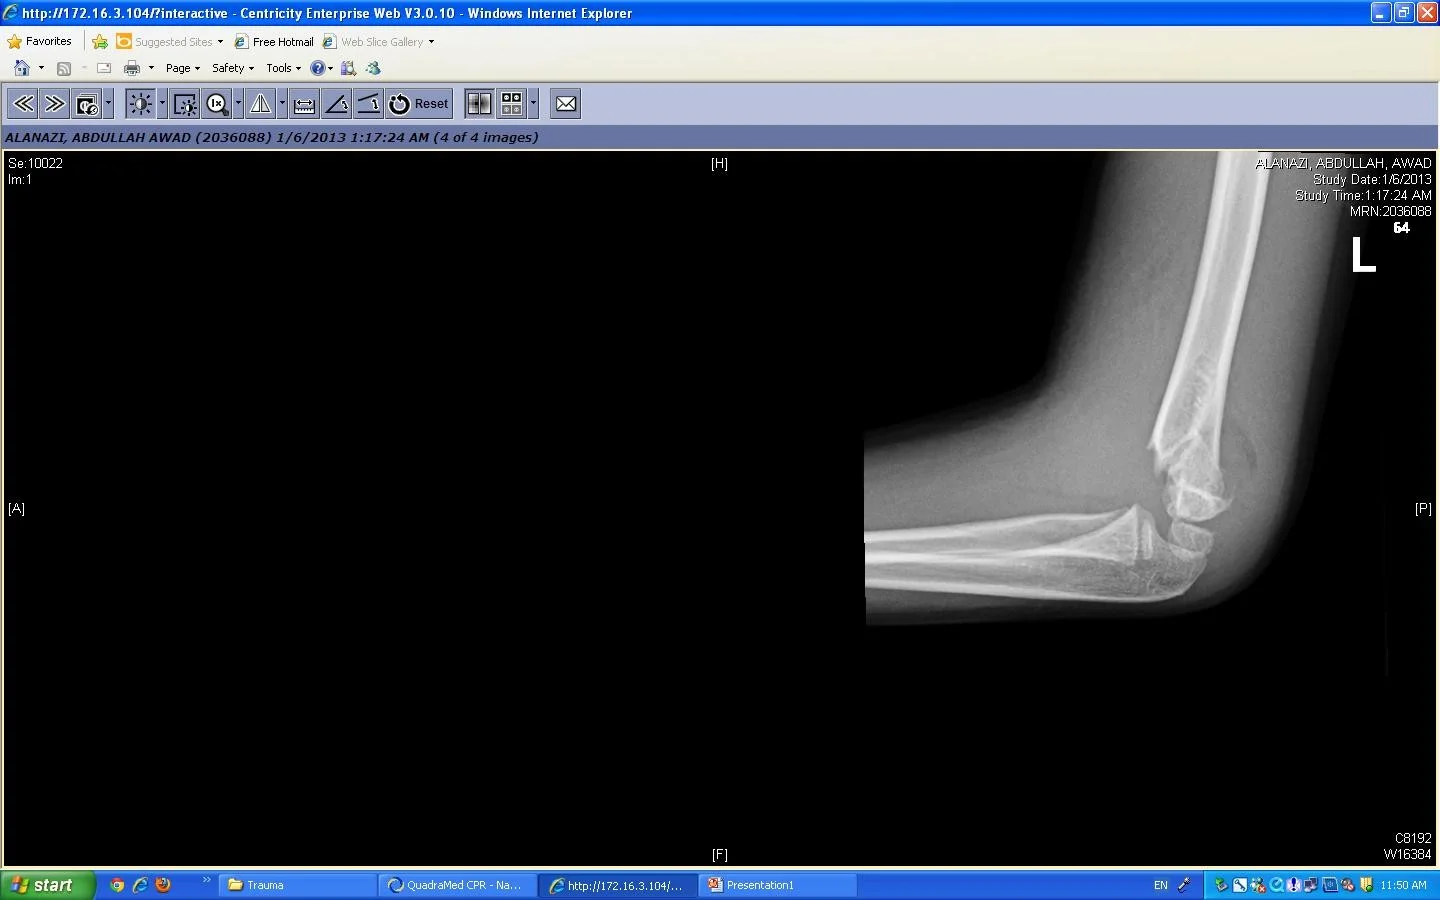

Trauma

- Trauma